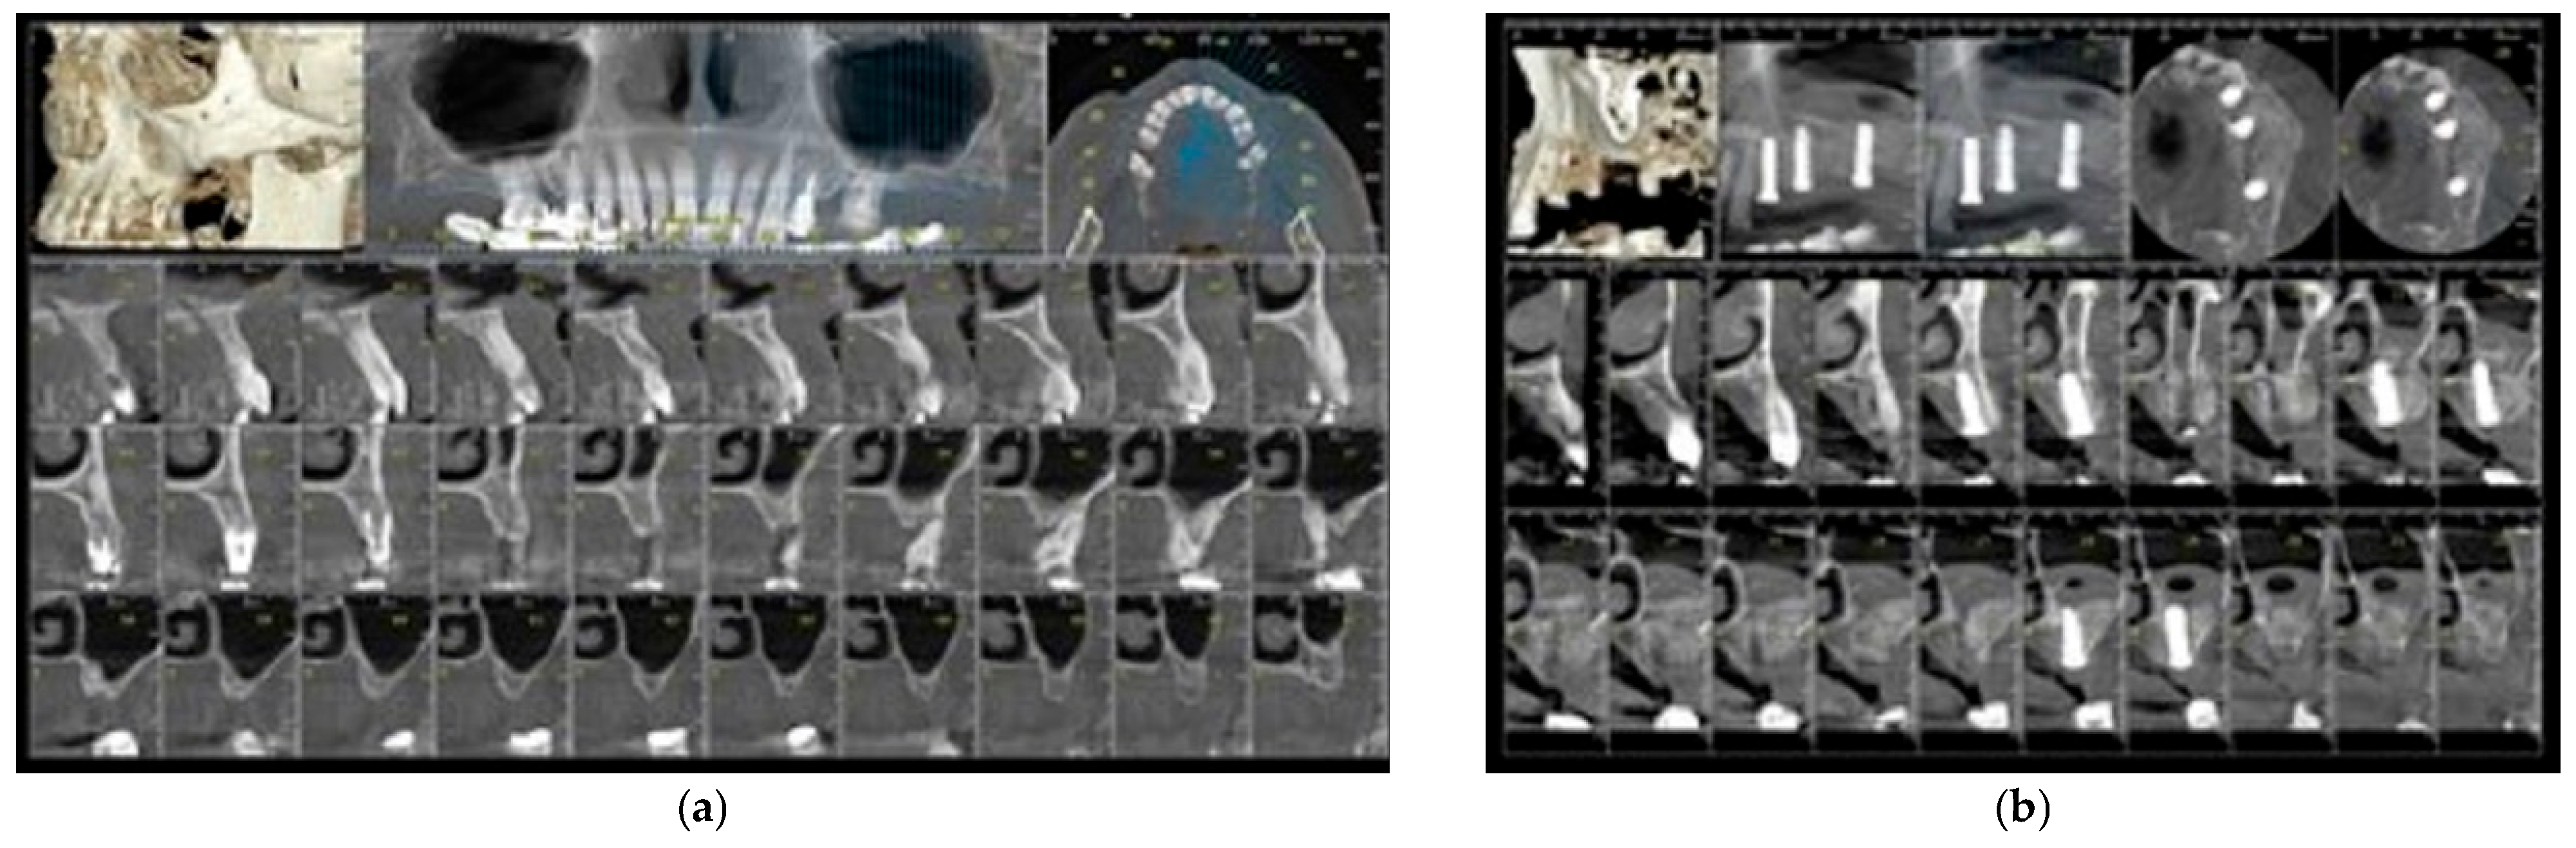

| 1. | F | 49 | 24 May 2021 | Lateral sinus lift with staged implantation | none | none | 4.7 | 2.5.; 2.6.; 2.7. | 2 | 15 | 13 | 52.23 |

| 2. | M | 56 | 9 August 2021 30 November 2021 |

| Intentional perforation for mucocele removal | none | 3.7 | 1.5.; 1.6.; 1.7. | 1 | 10 | 9 | 49.73 |

| 3. | M | 46 | 22 July 2021 | Lateral sinus lift with staged implantation | none | 7.5 | 2.6.; 2.7. | 1 | 15 | 14 | 38.3 | |